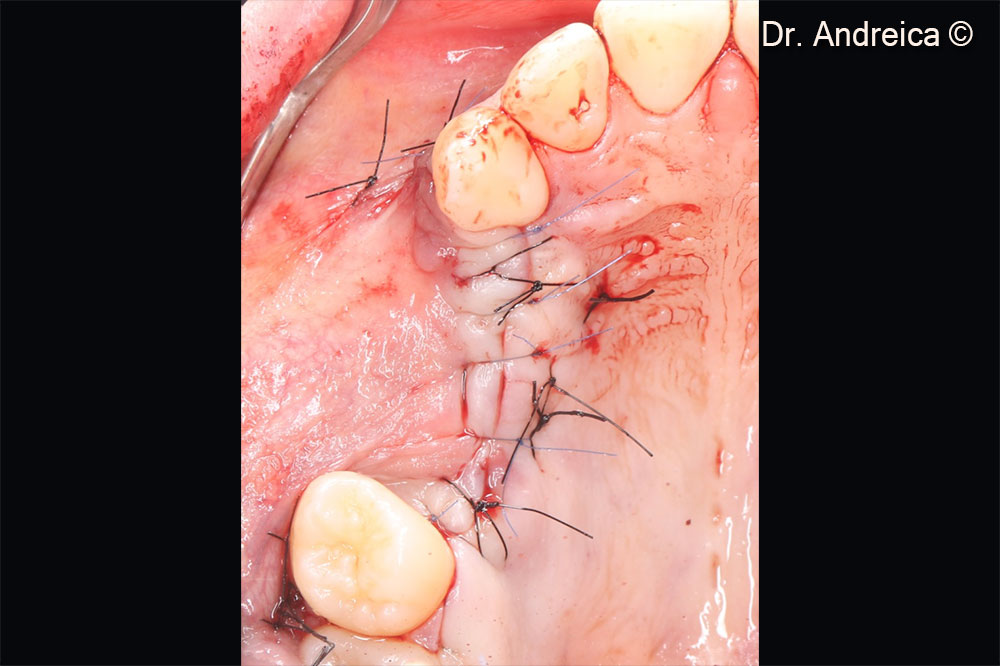

Tension free closure after periosteal releasing incisons, with Laurell-Gottlow and simple sutures